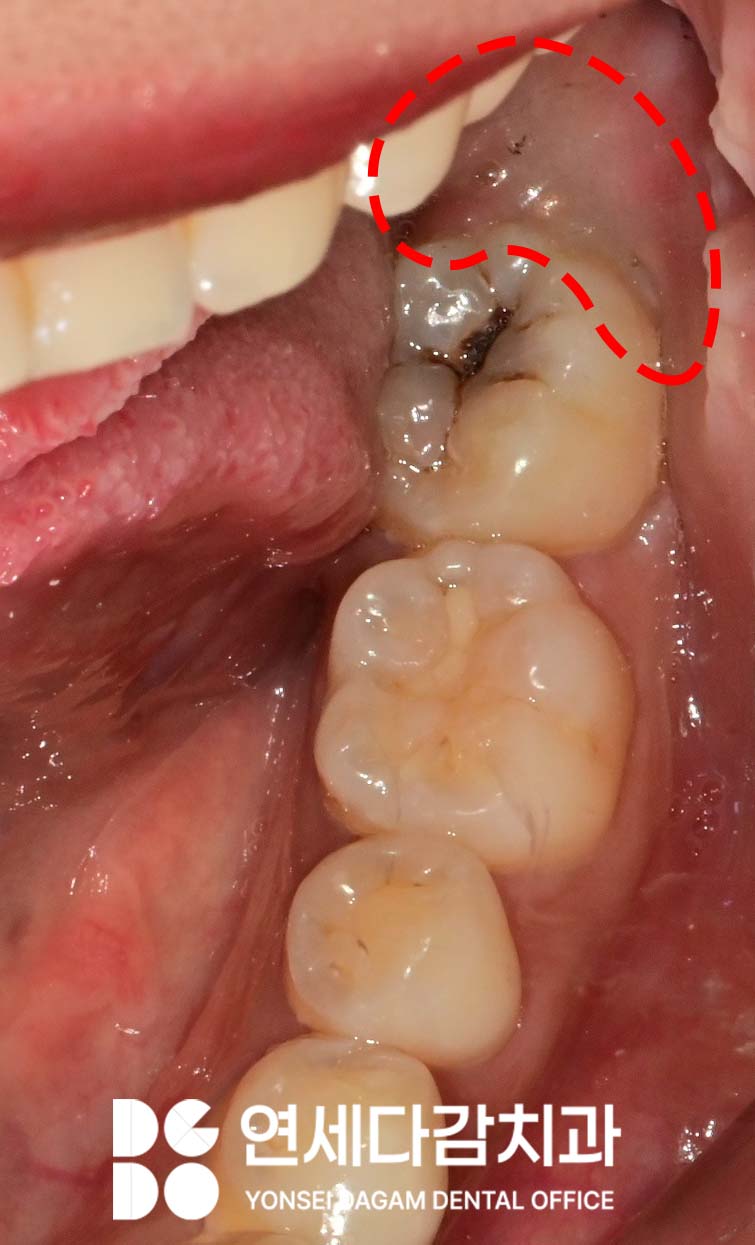

구강 검사 결과,

아래 매복 사랑니 주변으로

특히 심한 부종이 관찰되었으며,

해당 부위를 촉진했을 때

고름이 나오기도 했습니다.

이는 감염(지치주위염)이 진행 중임을

나타내는 명백한 징후였습니다.

추가로 위쪽 사랑니 부위에도

음식물이 자주 끼고,

평소 위생관리에 어려움을 겪고 있었습니다.

또한 어금니 중 하나는

심한 인접면 충치가 발견되었습니다.

충치가 치수(신경)에 도달한 것은 아니었으나,

범위가 넓게 퍼져있어

그 부위를 모두 제거하면 치관의

상당 부분이 사라지게 됩니다.

따라서 레진 코어를 통해

치관 구조를 재건한 뒤 크라운을 씌워

보호하는 것이 좋다고 판단되었습니다.